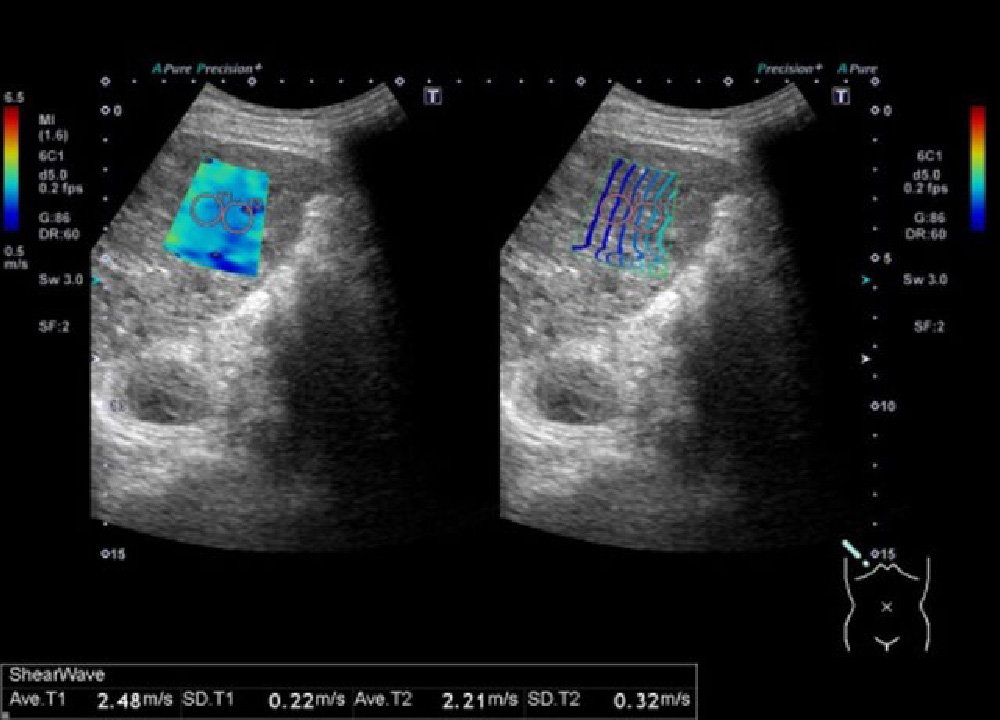

フィリップス、「Liver Fat Quantification(肝脂肪化定量評価。肝臓がん|消化器|診療内容|医療法人 甘木第一クリニック。肝臓がん|消化器|診療内容|医療法人 甘木第一クリニック。sakuraさん専用 蔵王吊るし柿4kg 紅干し柿 600g。Contrast Enhanced Ultrasound (CEUS) | フィリップスヘルスケア。Liver Ultrasonography | SpringerLink。キヤノンメディカルシステムズ、『肝臓の脂肪量の汎用超音波画像。Imaging Features of Hepatocellular Carcinoma in the Non。Imaging Features of Hepatocellular Carcinoma in the Non。714cFtk9QyL._AC_UF350,。肝臓病変における超音波の最新情報-第24回腹部放射線研究会。KMS_M01_XXX_670.jpg。腹部の超音波検査健康なヒト胆嚢 - 胆嚢のストックフォトや画像。